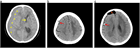

急性硬膜下血腫

1. 頭部外傷受傷直後から片麻痺等の神経症状や意識障害が持続する場合には、急性硬膜下血腫の存在を想起し呼吸・循環管理を行いつつ速やかに頭部CT撮影を行い診断する。

1. 抗血栓薬内服中の高齢者では軽微な外傷でも受傷することがあり、急速な意識障害の進行や亜急性の経過をとることもあり注意を要する。